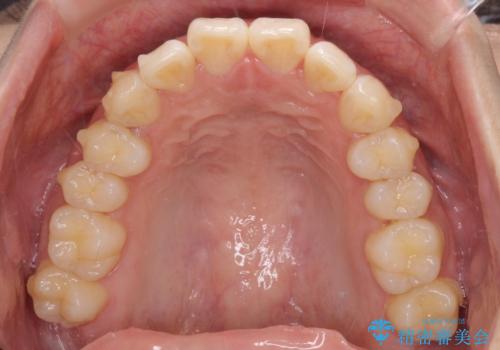

上下前歯の叢生をインビザラインできれいに

- 前歯のデコボコを気にして来院された患者様です。

前歯が重なっていることで口元が閉じにくくなっていたため、歯列全体の側方への拡大と、歯と歯の間を少し削ってスペースを獲得することとしました。